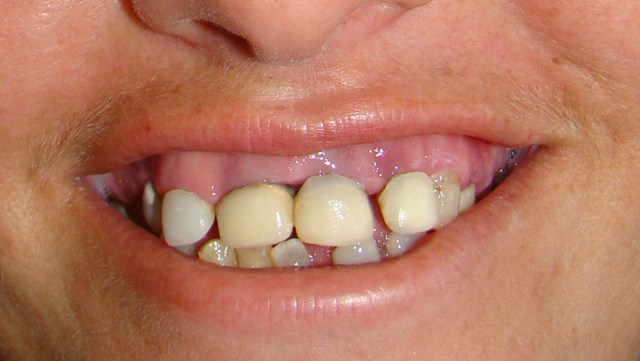

» Caso 5 - Reabilitação com implantes e dentes

Neste caso o paciente apresentava algumas ausências dentárias e algumas coroas meta...